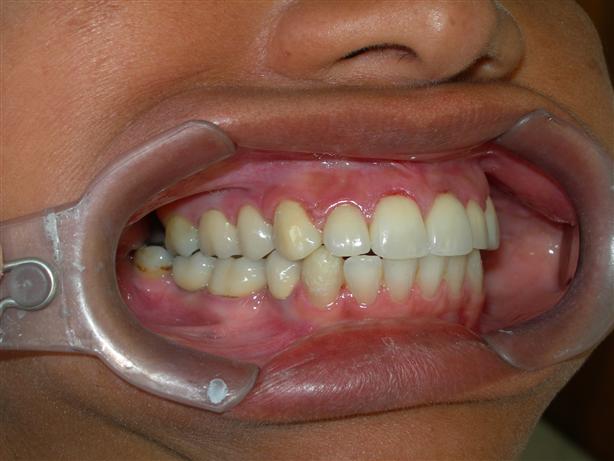

Caso concluído com próteses

metalocerâmicas cimentadas

Caso concluído com próteses metalocerâmicas cimentadas